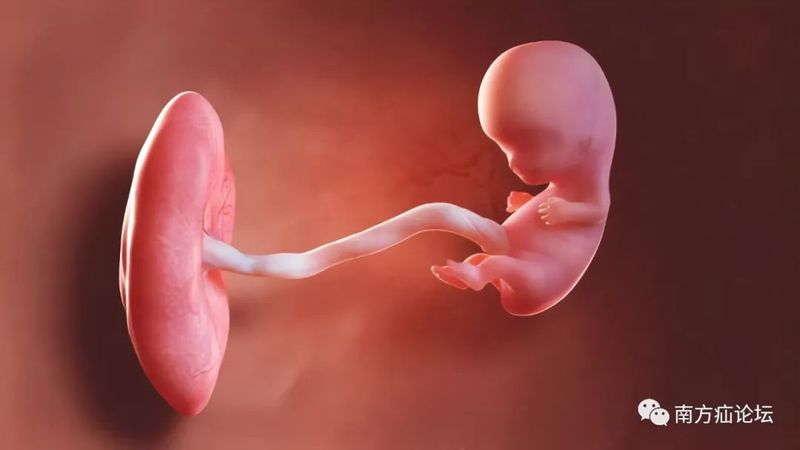

今天的故事從肚臍開始。臍,位于前腹壁上居中的一個結構,是人類在胎兒時期與母親連接的唯一門戶(臍帶,或稱臍索),在出生后臍索會“瓜熟蒂落“,脫落后留下的疤痕遺跡就是你腹壁上的臍。換句話說,人類有“臍”結構,這是胎生的證明,說明你有母親,是有媽的孩子!不像孫吾空,是從石頭逢里蹦出來的。所以,從“臍”這個結構的角度來看,無論如何贊美我們母親之偉大,都不為過。(圖胎兒、臍索和胎盤)臍疝在嬰兒中是常見的,在嬰兒中,當嬰兒哭泣時,臍疝可能特別明顯,導致肚臍突起。這是臍疝的典型癥狀。到了兒童時期,臍疝通常在出生后的頭兩年隨著生長發(fā)育自行閉合,盡管有些在第五年或更長時間內(nèi)仍然有疝囊,有開放的潛能,但不能為手術指征。成年期出現(xiàn)的臍疝才更可能需要手術治療。這是為什么?這里面可能又藏著好些個值得好好研究的問題?;氐浇裉斓闹黝},我們講的是外科歷史和人文,講的英國的歷史。打開外科學的歷史,里面腥風血雨,特別是外科剛剛開始的時候,很黑暗,很多事情讓當今的世人感覺不可思議。這里我們簡要回顧一下英國的歷史,說宗教對英國還是非常重要的。??在15世紀到16世紀歐洲各國之間混戰(zhàn),有人說歐洲的前三場戰(zhàn)爭,是法國路易十四建立了霸權,于1680年開始,成為歐洲至高無上的霸主。但接下來的后兩場大戰(zhàn),歐洲各國團結起來,抗擊路易十四霸權。與路易十四對陣荷蘭、英國、西班牙、羅馬帝國等國的組成了反法大同盟軍,最終將法國被打到破產(chǎn)。西班牙國王位繼承戰(zhàn)爭,爆發(fā)于1701年,一直打到1714年。反法大同盟軍的統(tǒng)帥成了英國威廉三世,英格蘭國王、蘇格蘭國王、愛爾蘭國王等在英國威廉三世的率領下。繼續(xù)戰(zhàn)爭。威廉三世在位末期,身體狀況不佳,(威廉是基督教徒,但此時皇親國戚與歐洲各國聯(lián)姻大多是天主教徒)1701年,英國政府為避免天主教徒繼位為王,頒布了《王位繼承法(1701版)》,規(guī)定,天主教徒不得繼承英國王位,因此,格奧格的母親蘇菲婭,作為基督教,成為英國王位繼承人。英國女王安妮駕崩無嗣,所以向下,排在今天主人公之一的喬治?(George)之前的,還有五十位血緣關系,但他們都是天主教徒,依據(jù)法律不能繼承英國王位。所以喬治母親蘇菲婭去世后,喬治(George)基督教就是血緣和安妮女王最接近的基督教徒了,這樣理所當然,安妮女王去世,喬治得以繼承英國王位,稱喬治一世(George?I)。這里要說,喬治一世他是以德語為母語的英國君主,換言之他根本不懂英語,也不會說,聽不懂,也不看英文,于是,他下令以輝格黨領袖斡博爾爵士為內(nèi)閣首相,主持各種事務,他作為國王則不出席內(nèi)閣會議了。從此英國開創(chuàng)了先例,國王不再出席內(nèi)閣會議,改由一名國王的親信大臣(首相)參加,這便成了英國首相制的開端。英國的漢諾威朝(1714到1901)延續(xù)近兩百年。漢諾威朝是英國歷史上最偉大的朝代,漢諾威朝時期,建立了大英帝國即英格蘭、蘇格蘭、愛爾蘭統(tǒng)一。漢諾威朝,六代帝王。王朝前期,就稱為喬治王時代,有喬治一世、喬治二世、喬治三世、喬治四世,連續(xù)五代。其實,喬治一世、喬治二世其實都是德國人,都不會說英語,以后的各王,才是在英國出生長大的英國人。今天故事的開頭要從1683年始,英國老國王喬治一世和王后索菲亞在這一年兩人終于生出了他們的獨生子取名GeorgeAugustus,,但他的出生地也不在英國,而是生于德國漢諾威(1683年10月30日)。這年是中國的農(nóng)歷癸亥年(豬年)已經(jīng)是清代康熙二十二年),直到1705年,他為了繼承王位,才入籍英國,1705年,他與勃蘭登堡的卡羅琳公主(Caroline)結婚?;楹笏麄冇兴膫€兒子和五個女兒,但多數(shù)都英年早逝。喬治二世頭像的英鎊喬治二世畫像故事的主人公是喬治二世的夫人,卡洛琳(Caroline),卡洛琳出身貴族。當1705年喬治二世與卡洛琳到達時英國時,這個原在德國家庭,發(fā)現(xiàn)他們在英國生活的氛圍才非常時髦。當時有階層的人多帶假發(fā),人們將這個時代命名為“格魯吉亞時代”。剛入英國,王室成員間互相用法語交談,在公共場合用帶有濃重德國口音、他們聽不懂的英語。英國的兩個喬治王,治理國家都是一般般,是出了名的“推遲綜合癥患者”,對他們的評價都是粗野、遲鈍、喜怒無常。卡洛琳而當時的國王完與公主卡洛琳則完全相反。她有趣、迷人、機智、美麗,卡洛琳還斡旋于政治,對于喬治二世的王位繼承非常重要。成為王后和她的侍女們成為英國王室魅力和風格的頂點。當時上流社會流行曼圖亞裙,曼圖亞裙這是一種奇形怪狀的裙子,兩側臀部有巨大的延伸部分,由鯨魚須加強筋作為支撐的,它的寬度如此之大,以至于女士們在穿過敞開的門時必須側著身(下圖所示)。這主要是為了顯示她們的腰很細。她們還會在頭上戴一個很高的帽子,在脖子和臉上涂上一層很厚的有毒鉛顏料,在嘴角上方畫上一個黑色的美人痣。然后,她們會被塞進由兩個走卒扛著的只能容納一個人的轎子里——連同假發(fā)、衣服等等,她們在倫敦的各個舞會和社交舞臺上跑來跑去。1727年夏天,老喬治一世在前往Osnabrück的馬車上死于中風。同時,新國王喬治二世和他的妻子卡洛琳王后等了13年才登上王位。在13年的奢侈和無所事事中,曾經(jīng)那么美麗的卡洛琳已經(jīng)變得肥胖得無可救藥。轎子根本坐不上了,甚至穿裙子也困難。雖然她的真實尺寸從未在肖像畫中出現(xiàn)過,她巨大的胸,名聲最終比她在現(xiàn)實中更大,但當卡洛琳最終成為王后時,她是如此巨大的王后,據(jù)計截她的太胖了以至于要幾個仆人的幫助她在床上翻身。而她的丈夫,國王喬治二世,卻找了個情婦(就是妻子的侍女首領)。在那個年代,王后卡洛琳可能并不為自己的暴飲暴食或由此而橫向發(fā)展的身材感到羞恥。甚至普通市民可以在周日買票觀看這對皇室夫婦用餐。人們可以看到女王,她的巨大肥胖的身體,自顧自的吃東西。她還有一個只有她丈夫知道的秘密。由于超重和多次懷孕,在生下小女兒露易絲公主后,她的腹部中部開始隆起,即臍疝。她巧妙地把這個凸起藏在衣服下面。這是一個臍疝,最終增長到一個“巨大的尺寸”。沒有人知道它到底有多大,但是,特別是對于超重的人來說,臍疝可以是巨大的,比如像西瓜那么大。臍疝病人,當腸子或內(nèi)臟通過臍部的缺損在腹壁肌肉中從腹腔中突出時,臍疝的表現(xiàn)就明顯。臍是在出生后留下的,通常不到半厘米,臍環(huán)也小到足以承受腹部的壓力。然而,如果腹部內(nèi)容物長時間膨脹,例如由于過多的脂肪組織或多次懷孕,臍環(huán)強度會減弱,被拉伸過大時腹腔的內(nèi)容物可以通過擴大的開口被推入;隨著時間的推移,腹內(nèi)內(nèi)容物可以推出的越來越多。如果臍口繼續(xù)變寬,突出的腸子在疝中保留足夠的空間不被卡壓。隆起只會造成不方便的觀感不佳,但當腹部壓力突然上升時,比如咳嗽、打噴嚏、大笑或緊張時,疝環(huán)卡壓住疝內(nèi)容物才會感到疼痛。若此時患者仰臥時,因重力影響作用會降低疝內(nèi)的壓力,使疝內(nèi)容物腸子回到腹部原來的位置,腫脹消失,直至患者再次站起來。這種自行或位體性的還納復位對病人的生活影響不大。但如果有更多的腹部組織進入疝囊。癥狀會加重,直到患者仰臥時腫塊也不會消失的程度,換言之,臍疝不能再復位了,疝的病程走入了死胡同,如果更多的腹部內(nèi)容物被迫進入疝,它會變得嵌頓,會引起突然劇烈的疼痛和嘔吐。此外,如果不采取措施減少臍口的壓力,疝囊中的組織就會壞死、絞窄。絞窄性臍疝的結果取決于被絞窄的是哪種組織,哪位外科醫(yī)生處理這種問題,尤其是他在什么時候這樣做。1737年的夏天,王后卡洛琳的腹部曾有兩次劇烈疼痛,但兩次都自行好轉(zhuǎn)并消失了。秋天后,11月9日星期三上午,她再次經(jīng)歷了極度的疼痛,這些情況在約翰·赫維勛爵、溫斯·張伯倫,皇室夫婦的私人朋友的回憶錄中有詳細的記錄。王后的疼痛劇烈,難以忍受,并伴有嘔吐。然而,那天晚上她還是堅持要像往常一樣出現(xiàn)在客廳里。晚上,她繼續(xù)干嘔,甚至不能靜靜地躺著,仆人給她喝的薄荷水和草藥苦味劑癥狀沒有減輕,腹痛也沒有消停。最后沒有辦法,傳喚了將英國皇家外科,前來出診的醫(yī)生是約翰·蘭比(RANBY,JOHN(1703–1773)皇家外科協(xié)會的主任,他采取了激進的措施:醫(yī)囑是給王后卡洛琳喝威士忌,并立即給她放血12盎司(約等于351.2毫升)。第二天對外科醫(yī)生蘭比(Ranby)來說是忙碌的一天。他開始給王后放更多的血,因為王后她仍然沒有感覺好一點。記載此時他還得照顧卡洛琳的女兒卡洛琳,因為女兒在母親王后的床邊哭了很久,哭到流了鼻血。蘭比對如何治療這位痛苦的年輕女士胸有成竹。他也給王后的女兒也放了血兩次。與此同時,各種各樣的醫(yī)生對王后進行各種各樣的治療。他們讓王后將她腿上一整出水泡,讓她喝長生不老藥,又給王后灌腸,盡管沒有人知道她到底出了什么問題。這群醫(yī)生們的診斷是“胃痛風”。有治療組的其中一名醫(yī)生因為說王后可能無法康復,而被國王喬治二世扇了一耳光。周五早上,王后的下面又排血了便,但腹痛還在繼續(xù),她把吃的喝的都吐了出來。直到第二天,國王喬治二世感覺再也掩飾不住了,才向醫(yī)生們說出了王后的秘密。他說:我違背她意愿,并告訴蘭比醫(yī)生,說,王后她隱瞞了超過13年的臍疝。直到那時——她生病的第四天——病人才被醫(yī)生檢查出問題所在,蘭比感覺到她腹部的腫脹,立即又叫來了兩位外科醫(yī)生同行,一位叫布西耶。有經(jīng)驗的80多歲老宮廷外科醫(yī)生,和一位年輕的城市外科醫(yī)生約翰·希普頓。在這三個醫(yī)生照顧女王時,喬治二世開始接手管理妻子的財產(chǎn),情況發(fā)展致此,終于得到了皇室重視。醫(yī)生組里的老布西耶醫(yī)生建議做一個大范圍的手術,在疝深處切開臍部開口,這樣被絞窄的腸子就能被推回腹部。這表明這位上了年紀的外科醫(yī)生仍然擁有敏銳的外科思維,但這位老醫(yī)生,在當時的考量顯然走在了那個時代的前面,治療組里蘭比醫(yī)生反對這個建議,而希普頓醫(yī)生同意蘭比醫(yī)生的建議,所以結論是觀察等待(wachtingandwaiting)。然而,隨著時間的推移,病人的疼痛加劇了。到了傍晚時分,蘭比醫(yī)生提出了一個難以理解,妥協(xié)方案,即在疝的上方開一個切口,切口不能深過腹腔。晚6點左右,三位英國1737年的專家們圍著王后的床,在燭光下勇敢的為她做起了手術。王后習慣于睡在五張床墊上。這對三位外科醫(yī)生來說,一定是一項非常繁重的工作,他們不僅要在那堆床墊上彎下腰來,還要在病人的身體上彎下腰來。蘭比醫(yī)生的夾克被汗水濕透了。按原版書籍記載的那樣:就像三個外科醫(yī)生像在解剖室里處理一具尸體上一樣,他們切開隆起的肚臍的皮膚,(那個時間還沒有消毒和麻醉的觀念)試圖把現(xiàn)在可見的東西推回到女王的腹部。這一定是王后一生中最痛苦的時刻,沒有麻醉、沒有肌松劑醫(yī)生們?nèi)绾文茏龅??他們的努力都白費了。手術后接下來的更悲慘:這個國家至高無尚的,最著名的王后現(xiàn)在不僅有一個絞窄的臍疝,而且還有一個巨大的傷口。沒有無菌和抗生素的年代感染是無法避免的。盡管做手術的三位外科醫(yī)生很擔心——而且有很好的理由這種可怕的情況最終會如何結束,但他們忽略了王后的病情好轉(zhuǎn)的明顯跡象。據(jù)記載:如果腸子真的被嵌頓壞死了,卡洛琳肯定不能再活過那漫長的五天。死亡的腸壁會讓壞死細胞的有毒腸內(nèi)容物、消化液在幾個小時內(nèi)進入腹腔,而后吸收入血液。那會導致災難性的機體內(nèi)生物化學連鎖反應和炎癥風暴,會立刻破壞她體內(nèi)的所有系統(tǒng)。她會在兩天內(nèi)死去。但在11月13日的星期天,術后她仍然很有活力,非常清醒,對她床邊的人做出了回應。可能是切開了腹壁,腹壁上嵌頓被減壓了,當時嵌頓壞死的是碩大而肥厚的大網(wǎng)膜組織。不一定是小腸,兩者不同之處在于,盡管被嵌頓卡死的大網(wǎng)膜很痛苦,但卻沒有那么危險,因為與將要死亡腐爛的腸道相比,卡死的脂肪細胞液化后使受害者的疾病減輕了。周日,也就是手術后的第二天,外科醫(yī)生對疼痛的傷口進行了處理。因為他們現(xiàn)在白天看得比前一天晚上在燭光下看得更清楚了,他們突然注意到疝深處的受損脂肪組織。在那些日子里,傷口上的任何痛苦通常被認為是病人很快會死于壞疽的確切信號。因此,盡管王后殿下并不比前一天感覺更糟,也沒有其他跡象表明她即將死亡,但當場的三位外科醫(yī)生還是經(jīng)驗不夠,認為她只能活幾個小時了。國王喬治二世被叫去向她告別。國王傷心欲絕。他承諾永遠忠于他心愛的妻子,即使在她死后。而王后殿下卻勸告他再婚。國王喬治二世抽泣著,說了一句具有歷史意義的話:“Non,j'auraidesmaftresses”(不,我還擁有情婦!)王后卡洛琳大呼:“我的天哪,那又有什么區(qū)別!”。之后,外科醫(yī)生們又開始緊張的工作了。當清理傷口他們切除壞死組織時,他們再次沒有注意到傷口沒有排泄物流出的好跡象,這意味著他們上次手術切除的不是腸道。王后卡洛琳的好友,勛爵張伯倫·赫維對外科醫(yī)生處理病人及其親人情緒的冷漠態(tài)度越來越感到不安。就在幾個小時前,外科醫(yī)生們還宣布王后命不久矣,而事實上事情并沒有發(fā)生,那三個醫(yī)生表現(xiàn)得好像什么事也沒有發(fā)生。王后殿下臍部傷口痛苦對她的生命好像沒有直接影響,在接下來的幾天里,王后殿下又接見了政府首相和大主教。然而,她越來越虛弱。她仍然咽不下任何食物,還不斷地嘔吐。外科醫(yī)生每天都在給她做手術,處理傷口,切除壞死組織,后來又把手指伸進去,用探針探測,當然,所有這些都不需要任何形式的麻醉。在一次手術中,年邁的布西耶把蠟燭舉得離頭太近,導致醫(yī)生的假發(fā)起火。英國的報紙公布了這些一個個可怕的細節(jié),導致后來王后卡洛琳的案件被公開辯論,用Hervey的話說,“就好像她在(皇宮)里面被解剖了一樣”。直到11月17日(星期四),情況才真正變得更糟,當時她的腸子在換藥處理時肯定被戳破了。嘔吐加劇,傷口突然開始流出大量糞便樣物。當糞便從王后的肚子里噴涌而出,浸透了王后殿下的床單,流趟在她臥室的地板上時,東西大多,沒有辦法,王后殿下寢室的窗戶因為惡臭被打開了。然而,依然堅強的王后殿下又堅持了漫長的三天,于1737年11月20日星期天晚上10點卡洛琳王后殿下在骯臟、最悲慘的環(huán)境中死去。享年54歲。無論如何,這位卡洛琳王后殿下給英國的后人上了深刻的一課,在那個年代外科手術弊大于利的時代,唯一正確的治療方法是不做手術,觀察和等待”(wachtingandwaiting),所以,wachtingandwaiting的理念被刻入了英國外科醫(yī)生的骨子里,和基因里,若不信,你看看《歐洲的疝指南》里面一定會有“wachtingandwaiting”。除了王后之死,14年后,175I年12月19日,歷史在丹麥重演??辶盏呐畠褐宦兑捉z公主,,嫁給了丹麥國王,也成了王后。和她目前一樣,她很肥胖。在她二十七歲的時候,她懷著孕,和她母親一樣出現(xiàn)了嵌頓臍疝。一名外科醫(yī)生再次試圖挽救她,但卻徒勞無功。在和她母親同樣可怕的情況下,她失去了年輕的生命和孩子。外科醫(yī)生盡管在他的職業(yè)生涯開始時遭遇了這樣的慘敗,約翰·蘭比對自己的評價非常高。在1744年他出版的《槍傷治療方法》一書中,描述了自己在英國軍隊中擔任軍醫(yī)的最輝煌時刻。他的英雄事跡之一是對待威廉王子,國王喬治二世和已故女王卡洛琳的小兒子,也被稱為“屠夫”。1743年,在奧地利王位繼承戰(zhàn)爭期間,威廉和他的父親一起在德廷根戰(zhàn)役中對抗法國人。這是英國歷史上最后一次國王親自率領軍隊上戰(zhàn)場。威廉被一顆火槍子彈擊中,子彈直接穿過他的小腿,造成了一個“雞蛋那么大”的傷口。蘭比立刻沖過去幫助流血不止的王子,拔出了他的刀。今天,一個明智的外科醫(yī)生會切開士兵的褲腿來評估傷口,用褲腿做一個結實的加壓繃帶來阻止血液的流動,并盡快把受害者從混亂的戰(zhàn)斗中帶走。但蘭比用他的刀做了別的事。他在倒下的王子手臂上開個口子讓他流血,就在那里,在戰(zhàn)場的中央,火槍子彈在他們耳邊飛舞。他吸了超過半升的血,好像受害者的腿失血還不夠。在戰(zhàn)地醫(yī)院里,他用面包和牛奶包扎傷口,又讓王子流了兩次血。盡管如此,這個年輕人還是活了下來,這讓外科醫(yī)生感到非常榮幸和欣慰。后來,蘭比就不那么幸運了,因為他的治療方式很荒謬。他用放血療法幫羅伯特·沃波爾這個英國首相從尿道取出膀胱結石。在這里,他也想不出更好的辦法,就是再給病人放點血,盡管病人已經(jīng)失血過多以致快要死了。今天的故事告訴各位,作為外科醫(yī)生的你,也許對哲學不興趣,但哲學一定會深深地影響你。哲學教你如何思考方式,如何處理病人符合邏輯性。外科醫(yī)生一定要對其手術的下一步,或之后疾病的發(fā)展和應對的方法心中有數(shù),想清楚才能去做,不能無知而無畏去犯錯。英國媒體對卡洛琳王后之死的討論認為:在外科治療中,“觀察等待”(wachtingandwaiting)也是一種寶貴的工具,無論是在作出診斷還是在改善病人的健康狀況方面。這反映在外科醫(yī)生治療病人時可以采用的三種不同的方法上:1)保守治療(不進行手術干預)、2)預期治療(觀察等待而不進行治療)3)侵入性治療(通過手術干預事件的流程)。你看今天的歐洲疝指南一定寫了對無癥狀的疝可以“觀察和等待”(wachtingandwaiting)。換言之,我們從今天的故事中或多或少可以看到了英國或歐洲的醫(yī)生思維中還留下了300年前歷史的痕跡。